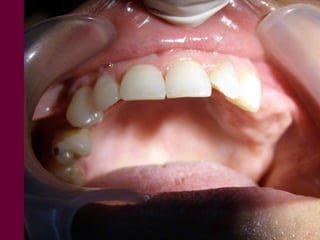

Conocer los diversos recursosprotéticos que dispone la odontología Prótesis fija Prótesis removible parcial Prótesis removible total Prótesis implanto-asistida